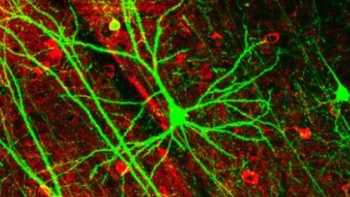

Imagen

El sistema nervioso entérico es encargado de controlar directamente el aparato digestivo.